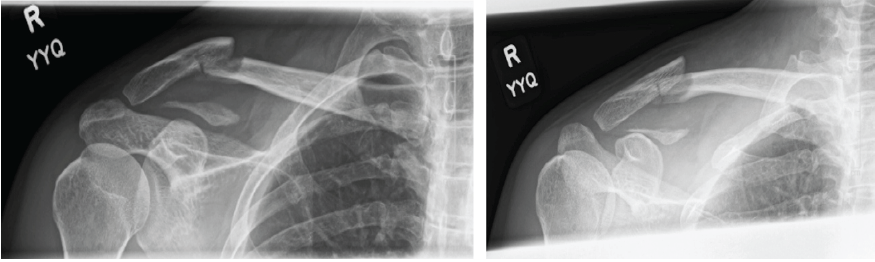

A 33-year-old right-handed male motorcyclist with a background of impaired fasting glucose on diet control was brought into the emergency department after a road traffic accident. The patient was travelling between 60 and 70 km/h along an expressway when the vehicle ahead braked suddenly. This resulted in the patient crashing into the rear of the vehicle and landing onto his right shoulder. In the emergency room, the patient complained of right shoulder pain with a deformity noted over the lateral aspect of the right shoulder without any overlying skin defect. A Neer Type V distal clavicle fracture was noted after dedicated clavicle radiographs were performed (Fig. 1). The patient was counseled and consented to the surgical fixation of his right distal clavicle.

Figure 1: Pre-operative radiographic imaging of right Neer Type V distal clavicle fracture.